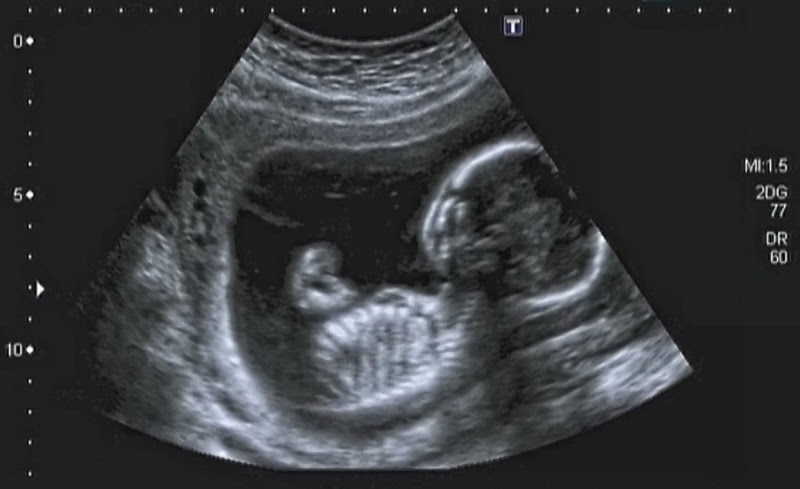

Jul 14, · エコー写真からわかること 妊娠12週目のエコー写真では、 胎児の体や手足の部位がはっきりとわかるようになります 。顔の形がはっきりとしてくるほか、まれに性別を判定できる場合もDec 26, · 早い人では妊娠12~14週で性別がわかったという人もいるようですが、一般的には、妊娠18~週頃に判別ができるようになるケースが多いようです。 エコー検査では、お母さんも実際に検査画面を見ながら先生の診察を聞くことになります。性別の事です。 以前こちらで性別の事を質問させてもらいましたが。 今日、34w4dの妊婦検診に行ってきました。 今まで、25wと27wは女の子っぽいねーって言われていて エコーでも、玉もちんも見当たらなくて 30wのときに